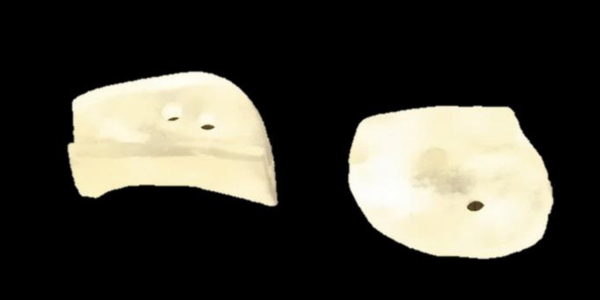

The implant consisted of two main components:

Mandible Component: Made from Ti6Al4V-ELI Grade 23. This material is well-known for its biocompatibility, strength, and corrosion resistance, making it suitable for load-bearing applications.